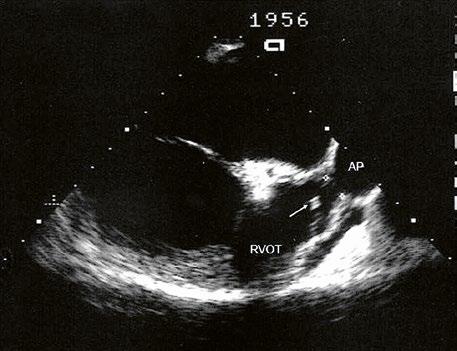

Supravalvární pulmonální stenóza a stenózy větví plicnice bývají součástí komplexních VSV (např. Fallotovy tetralogie) nebo syndromů (Williamsův syndrom, syndrom Noonanové, syndrom vrozené rubeoly, Alagillův syndrom aj.) (Obr. 45.39). Získané stenózy větví plicnice, ale i úplný uzávěr větve plicnice můžeme vidět po spojkových operacích podle BlalockaTaussigové (Obr. 45.40, Obr. 45.41). Pro zobrazení supravalvárních a periferních stenóz plicnice je optimální CT angiografie (Obr. 45.40, Obr. 45.41, Obr. 45.42, Obr. 45.43).

Obr. 45.39 TEE, valvární a supravalvární stenóza plicnice blízko nad chlopní, označena křížky. Valvární stenóza s domingem chlopně označena šipkou. AP – kmen plicnice za stenózou, RVOT – výtokový trakt pravé komory